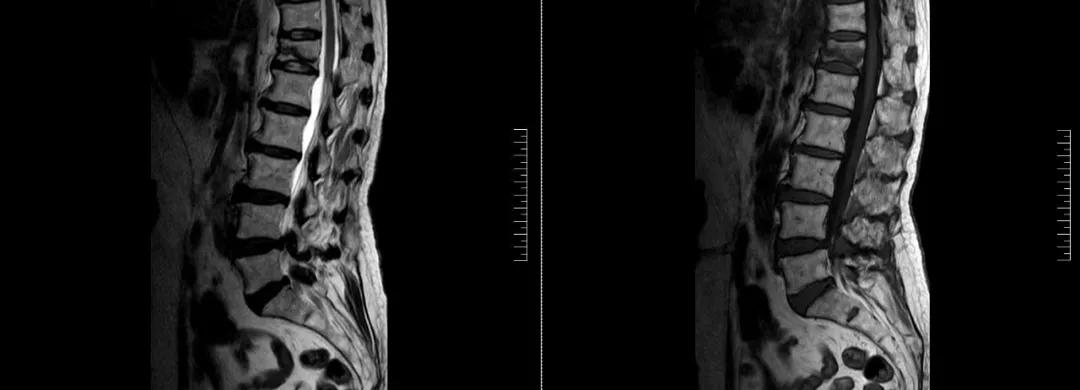

術(shù)前磁共振檢查提示腰1椎體新鮮壓縮性骨折